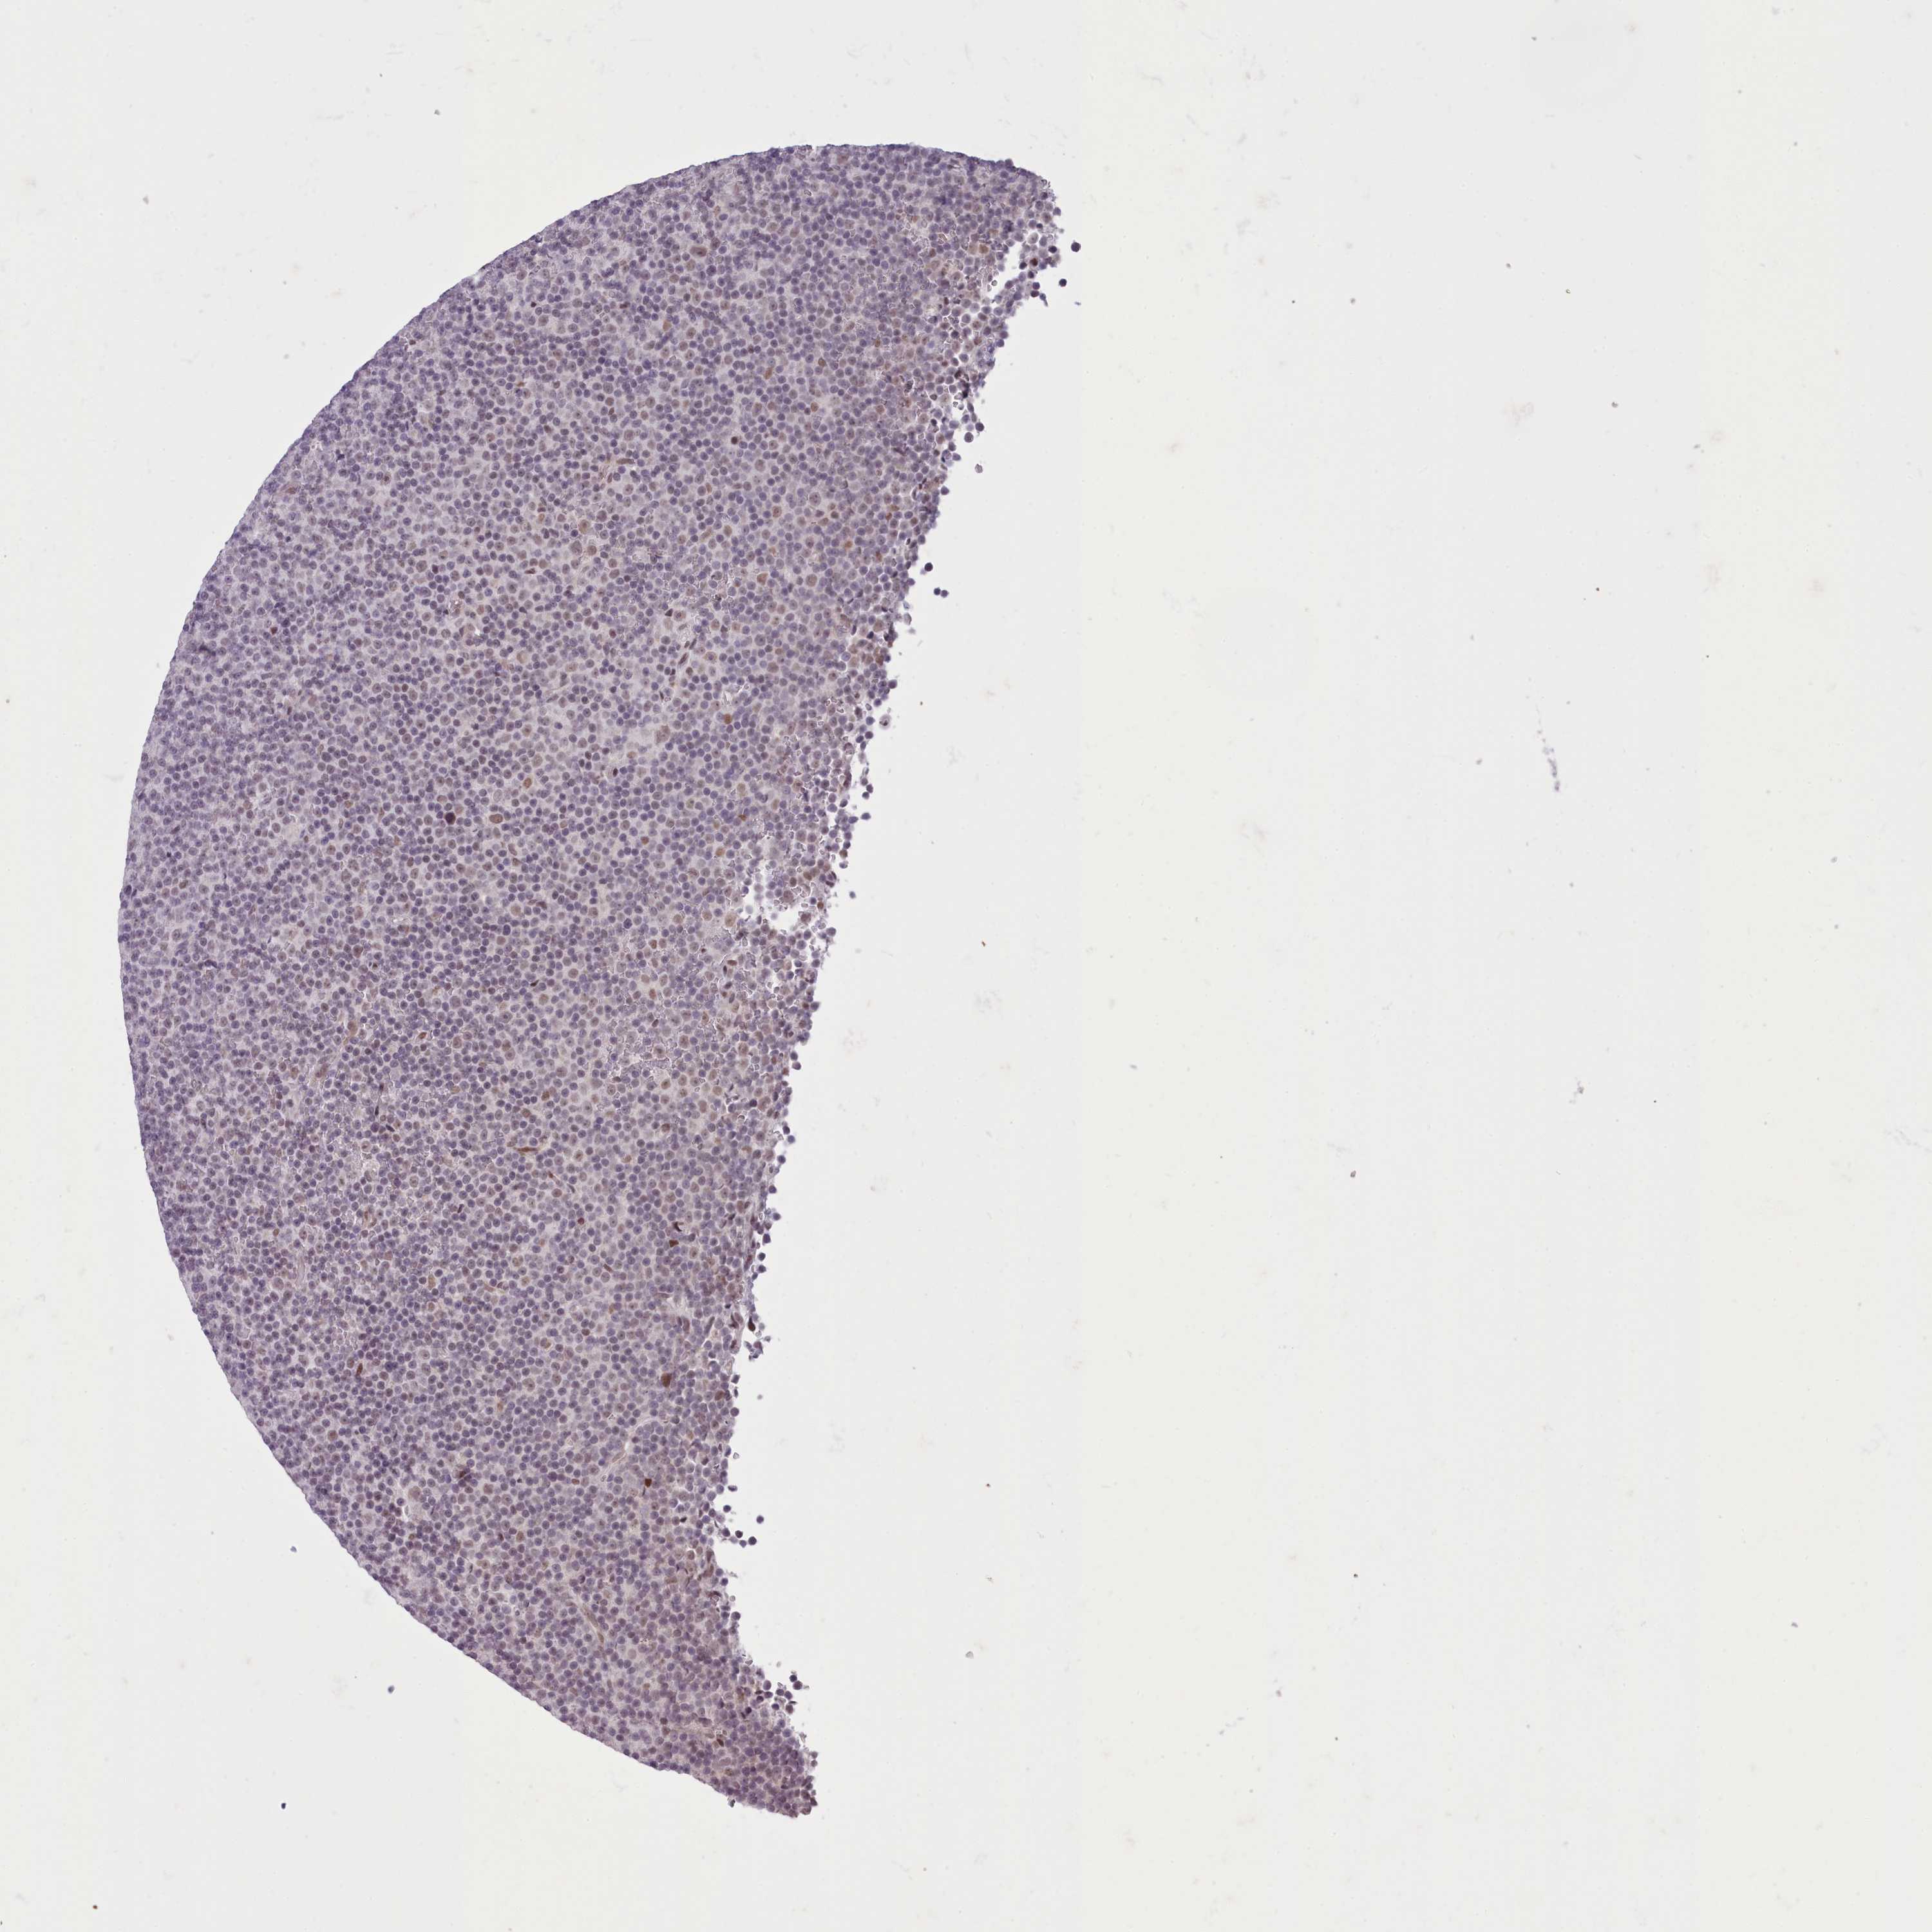

CANCER LYMPHOMA Show tissue menu

LYMPHOMA - Protein expressioni

A mouse-over function shows sample information and annotation data. Click on an image to view it in a full screen mode. Samples can be filtered based on level of antibody staining by selecting one or several of the following categories: high, medium, low and not detected. The assay and annotation is described here.

Each image is clickable and will lead to virtual microscopy that enables deeper exploration of all samples and also displays staining intensity scores, fraction scores and subcellular localization as well as patient and tissue information for each sample.

Antibody HPA048722

Hodgkin's disease, NOS

Malignant lymphoma, non-Hodgkin's type, High grade

Malignant lymphoma, non-Hodgkin's type, Low grade